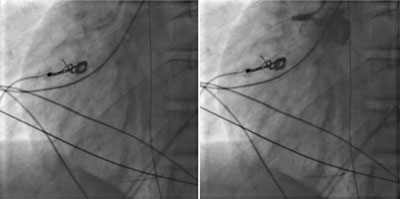

Figure 3

Coronary angiography. Left side image showing guide in the RCA. On the right-side image during injection of iodized contrast showing backflow in the aorta and no enhancement of the RCA compatible with complete occlusion.